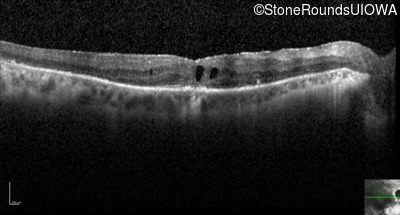

Optical Coherence Tomography - Left - 20/125

Exemplar / OCT Stack

OCT Stack